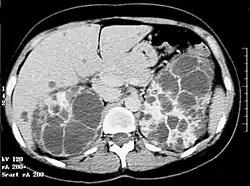

La polykystose rénale autosomique dominante (PKD), aussi appelée maladie rénale polykystique ou encore Rein polykystique autosomique dominant est la plus fréquente des maladies héréditaires monogéniques du rein. Elle se caractérise par l’apparition lente et progressive de kystes principalement au niveau des reins.

Les dilatations kystiques atteignent à la fois les canalicules biliaires et les néphrons. Les complications rénales de cette polykystose sont liées au développement, à la désorganisation, et à la destruction du parenchyme rénal normal par les kystes rénaux. La sévérité de l'atteinte rénale est directement corrélée au volume des reins. L’aspect « in utero » est rare et ressemble souvent à une polykystose rénale type récessif mais d’apparition est beaucoup plus tardive (vers 28, 32 semaines) avec absence d’anomalie du liquide amniotique. Une échographie rénale des parents est une aide pour le diagnostic. Tous les individus porteurs d'une mutation dans le gène PKD1 ou PKD2 développeront des kystes rénaux (pour les formes liées à PKD1, l'absence de kystes rénaux après 30 ans élimine le diagnostic.

Les kystes hépatiques sont fréquents et leur prévalence varie avec la méthode diagnostique utilisée (beaucoup plus fréquent à l'IRM, plus sensible, qu'à l'échographie. Ils sont le plus souvent silencieux.

Le scanner n'est pas nécessaire en première intention, même s'il visualise parfaitement les kystes, qu'ils soient rénaux ou hépatiques. l'IRM permet de quantifier le volume rénal, ce dernier étant corrélé avec le risque évolutif[16].